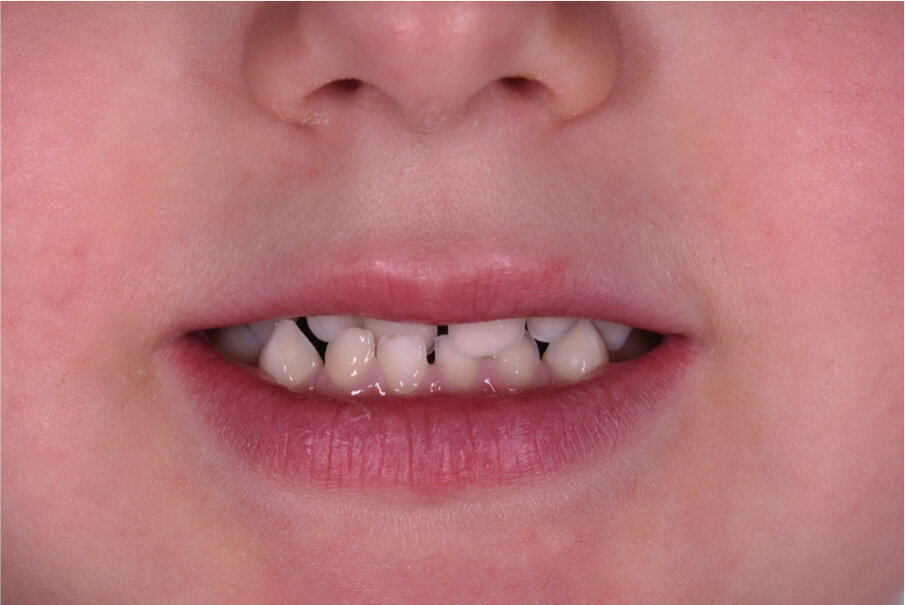

Caso 3 M.D.E Anni 2, succhiamento protratto del dito, deglutizione atipica, open bite dentale, contrazione arcata superiore. I genitori riferiscono difficoltà a respirare e raffreddori ricorrenti (Figg. 24-28).

Fig. 24

Fig. 25

Fig. 26

Fig. 27

Fig. 28

La paziente è stata trattata con un tipo particolare di AMCOP by Micerium a forma di “ciuccio”, il quale non richiede la presa dell’impronta, ideale per i pazienti in dentizione decidua e soprattutto per i pazienti di 2-3 anni con malocclusioni evidenti. I risultati sono stati ottenuti in 6 mesi di terapia, l’apparecchio è stato portato tutte le notti ed 1 ora durante il giorno. Dopo aver ottenuto il risultato l’AMCOP by Micerium viene portato per altri 6 mesi solo la notte per garantire la stabilità e per recuperare la funzione linguale e del muscolo orbicolare delle labbra.

Questo caso dimostra come la correzione della malocclusione funzionale, frequente nei bimbi a quest’età, sia il nostro primo obiettivo terapeutico.